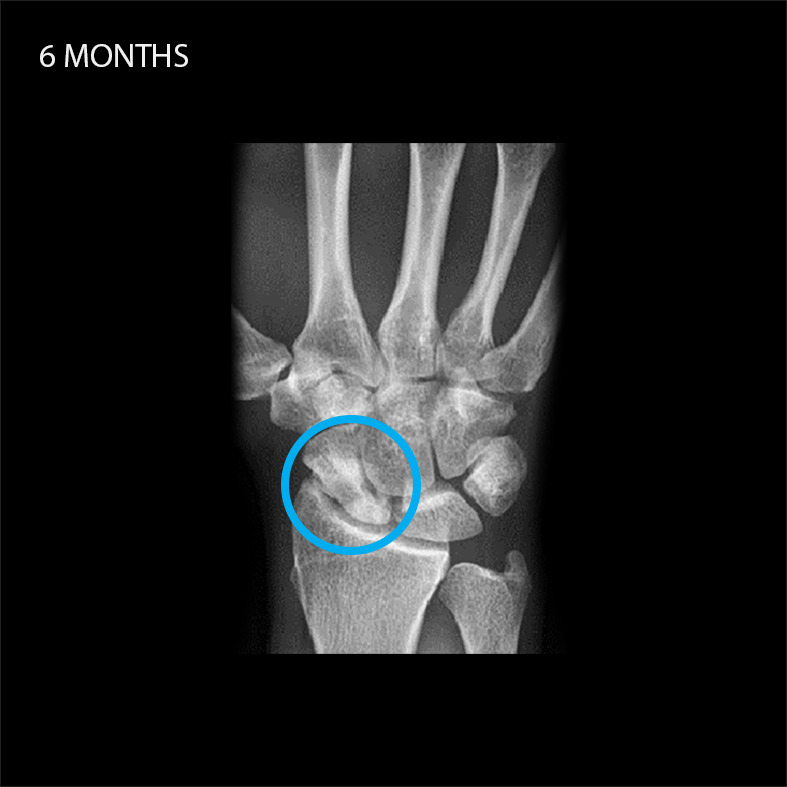

Case reports with Shark Screw®

Shark Screw® shows its full potential when it comes to non-union cases. The creeping substitution can significantly boost bone healing – just trust biology.

Shark Screw® can be used in the space of Foot & Ankle (e.g. bunionectomy, MTP1 fusion, Hammertoe correction, IP-Fusion, TN-Fusion, Lapidus Arthrodesis, Lisfranc Joint Fusions, Jones Fx, Weil Osteotomies, DIP Fusions, Non-Unions, Medial Malleolus Osteotomies, Calcaneus Osteotomies, Subtalar Fusions etc.). Shark Screw® can be also utilized in various indications in Hand & Wrist surgery (e.g. DIP and PIP Fusions, MCP1 Arthrodesis, Scaphoid Fx and Non-Unions, Metacarpal Fusions, Four Corner Fusions, Distal Radius Fx etc.)